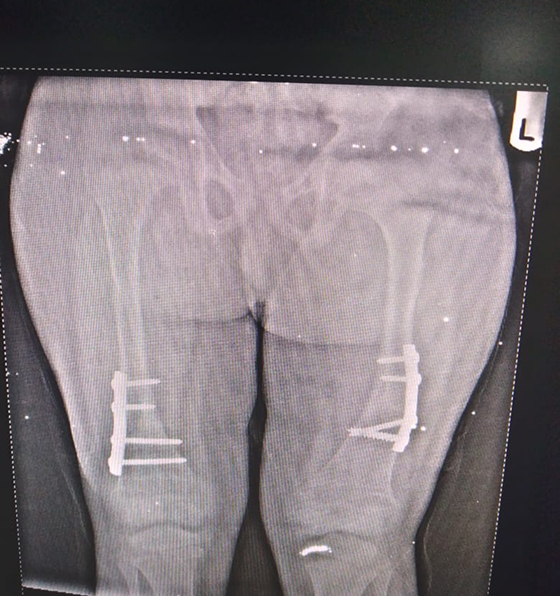

Caring for Growing Knees

Knee issues are common in children, ranging from sports injuries to growth-related alignment problems like knock-knees or bow legs. Early treatment prevents future pain and deformity.

We provide:

- Treatment for ligament injuries and meniscus tears

- Non-surgical care for alignment concerns

- Surgical correction for severe deformities

- Sports medicine for active children and teens

“From playground tumbles to sports injuries, every knee tells a story, we make sure it heals the right way.”